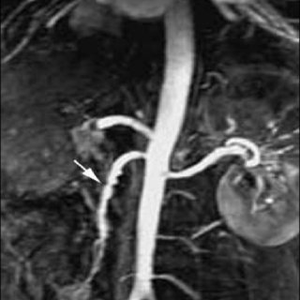

Se va lua în considerare un diagnostic de ischemie mezenterică cronică la pacienții cu următoarele simptome: